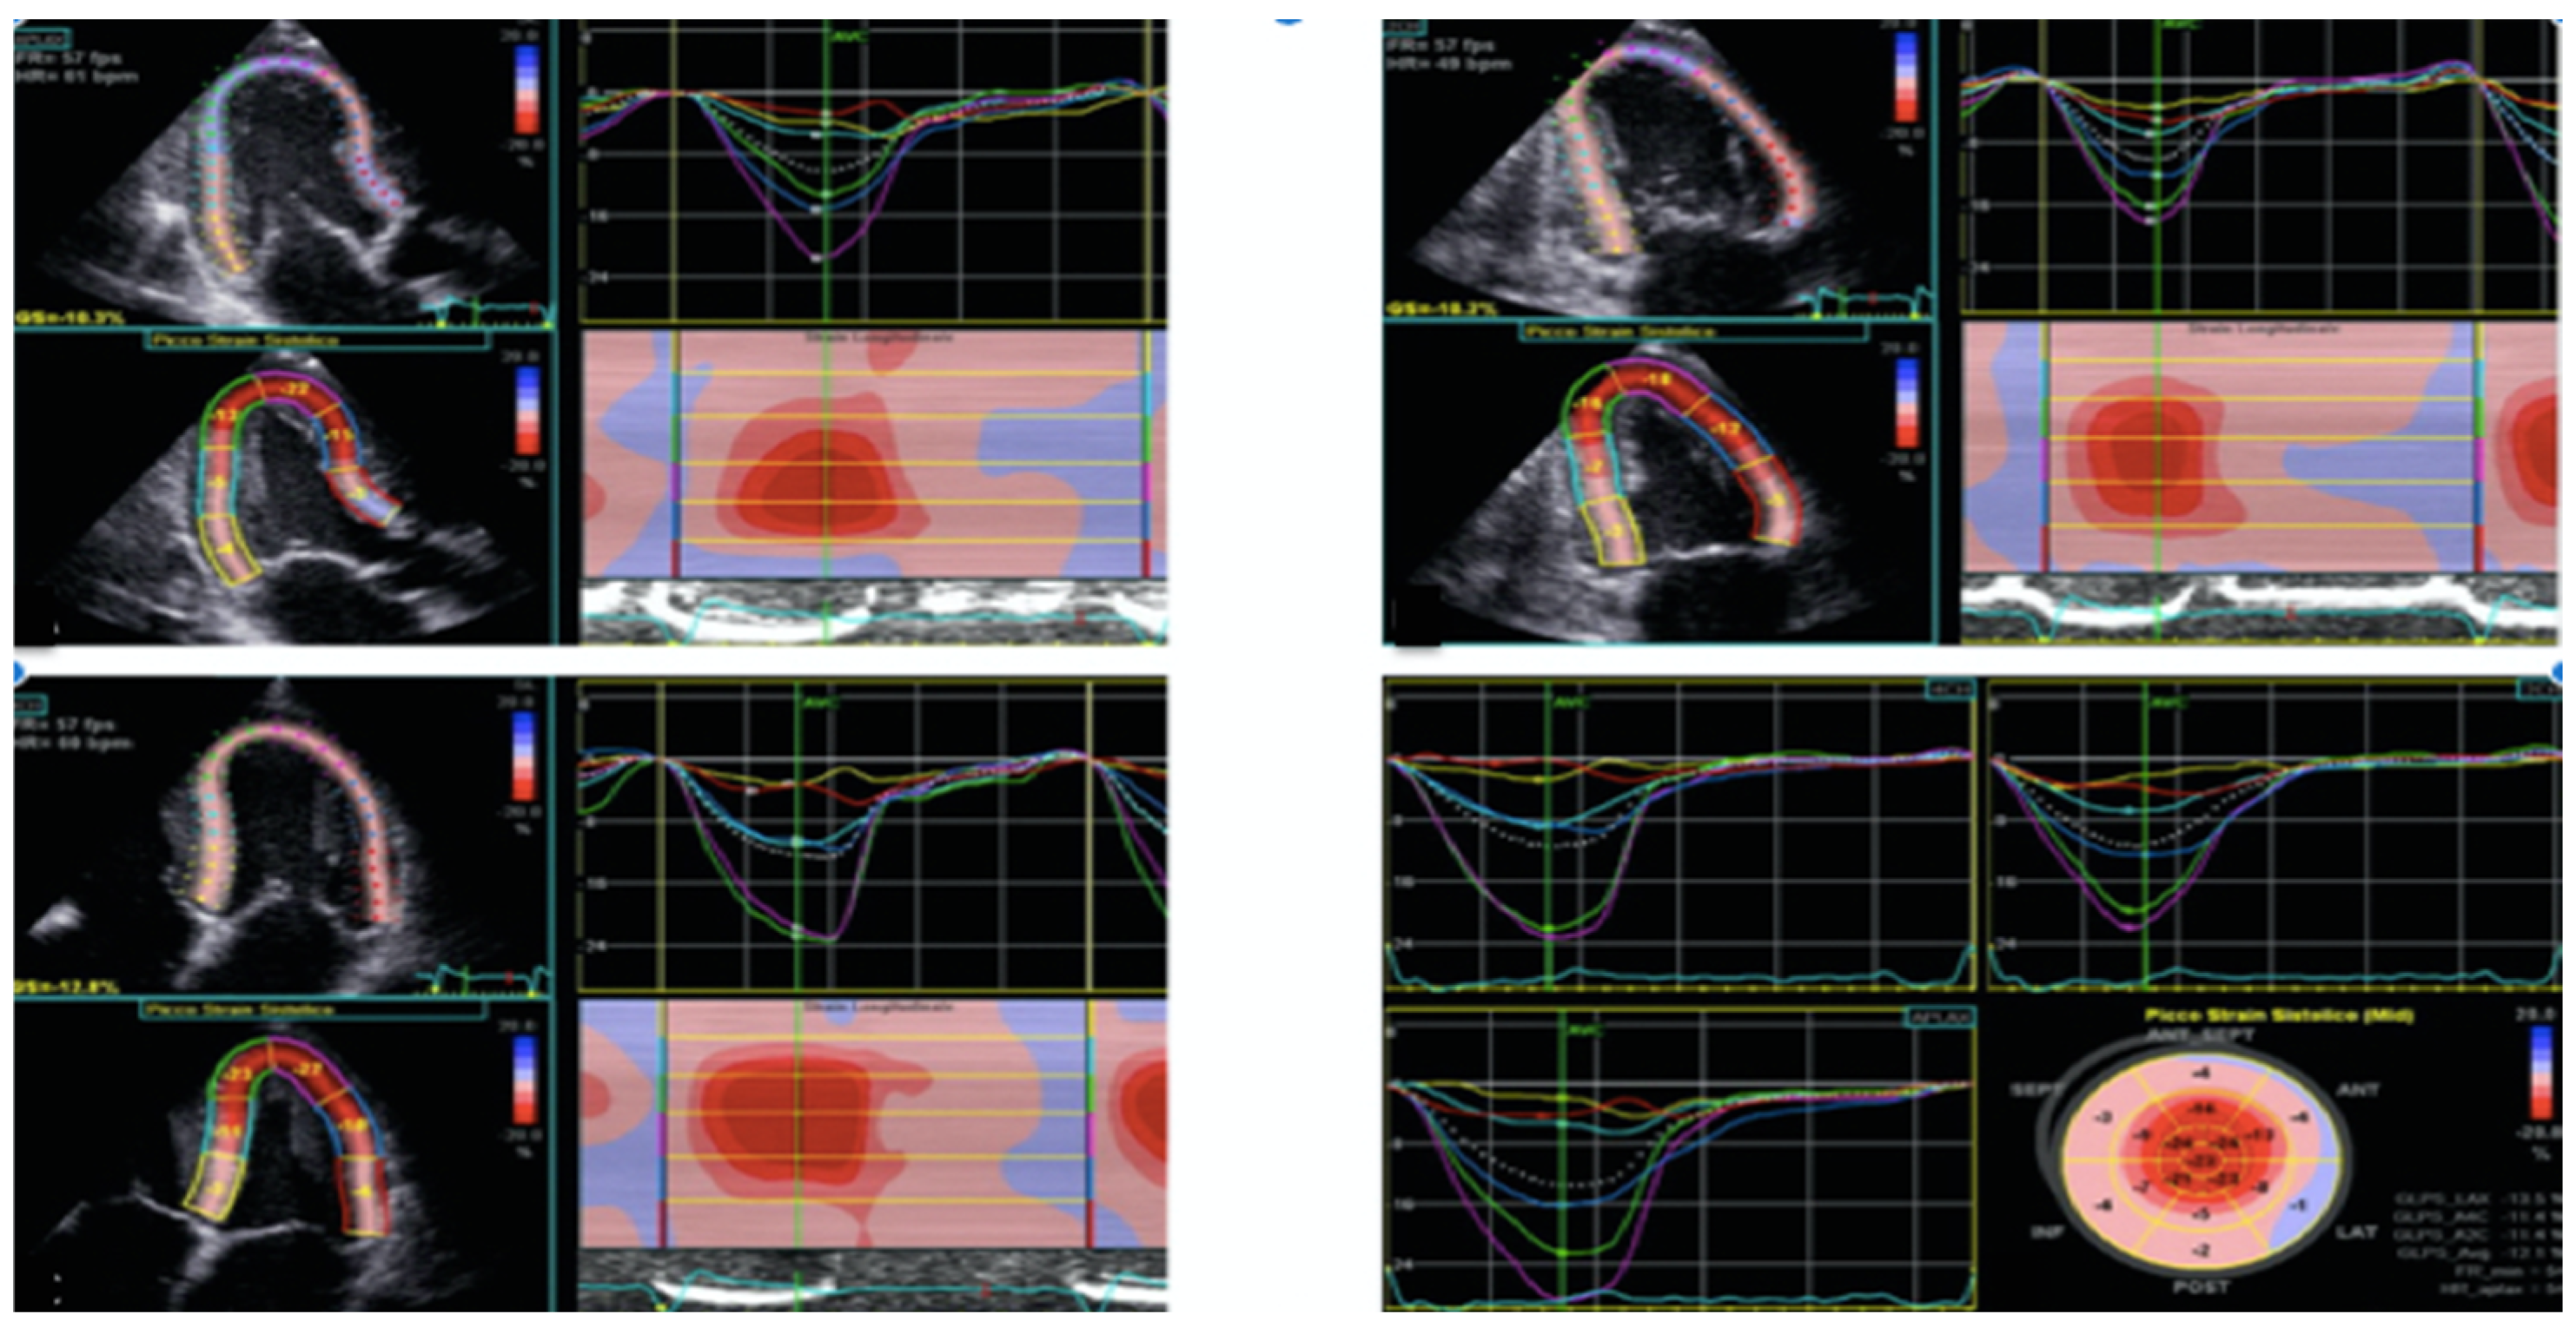

2.1. Echocardiography Evaluation

- Mondillo, S.; Galderisi, M.; Mele, D.; Cameli, M.; Lomoriello, V.S.; Zacà, V.; Ballo, P.; D’Andrea, A.; Muraru, D.; Losi, M.; et al. Speckle-tracking echocardiography: A new technique for assessing myocardial function. J. Ultrasound Med. 2011, 30, 71–83. [Google Scholar] [CrossRef] [PubMed]

- Voigt, J.U.; Pedrizzetti, G.; Lysyansky, P.; Marwick, T.H.; Houle, H.; Baumann, R.; Pedri, S.; Ito, Y.; Abe, Y.; Metz, S.; et al. Definitions for a common standard for 2D speckle tracking echocardiography: Consensus document of the EACVI/ASE/Industry Task Force to standardize deformation imaging. J. Am. Soc. Echocardiogr. 2015, 28, 183–193. [Google Scholar] [CrossRef]

- Cameli, M.; Mondillo, S.; Galderisi, M.; Mandoli, G.E.; Ballo, P.; Nistri, S.; Capo, V.; D’Ascenzi, F.; D’Andrea, A.; Esposito, R.; et al. L’ecocardiografia speckle tracking: Roadmap per la misurazione e l’utilizzo clinico [Speckle tracking echocardiography: A practical guide]. G. Ital. Cardiol. 2017, 18, 253–269. [Google Scholar]

- Rapezzi, C.; Fontana, M. Relative Left Ventricular Apical Sparing of Longitudinal Strain in Cardiac Amyloidosis: Is it Just Amyloid Infiltration? JACC Cardiovasc. Imaging 2019, 12, 1174–1176. [Google Scholar] [CrossRef] [PubMed]